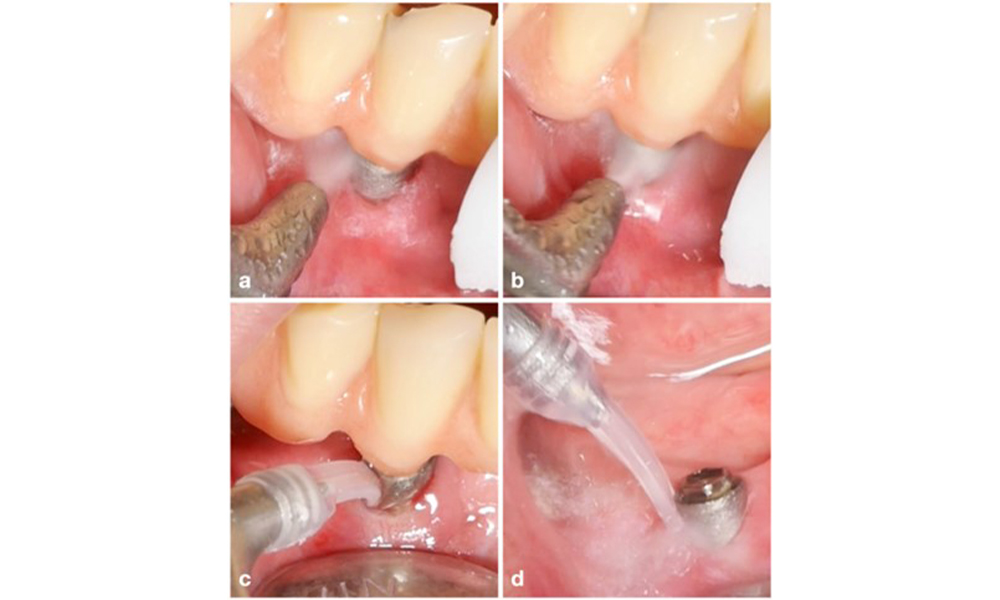

Management der periimplantären Mukositis

Das Behandlungskonzept der periimplantären Mukositis ist mit der Gingivitistherapie vergleichbar. Die wichtigste Maßnahme ist eine professionelle Plaquekontrolle mit dem Ziel einer mechanischen Entfernung des Biofilms ohne Veränderungen am Implantat oder an der Abutmentoberfläche. In der Literatur werden verschiedene Methoden unter Verwendung mechanischer Mittel beschrieben: Küretten, Schall- und Ultraschallscaler, Luftpoliergeräte, Laseranwendungen usw. mit oder ohne antimikrobielle Wirkstoffe. Derzeit liegen keine konsistenten Belege vor, dass eine Methode den anderen überlegen ist, und eine Behandlung der periimplantären Mukositis mit systemischen Antibiotika wird nicht empfohlen (Dommisch et al. 2022; Gennai et al. 2023; Hallström et al. 2012; Herrera et al. 2023; Verket et al. 2023).

Die Wahl der Mittel hängt von den klinischen Gegebenheiten wie zum Beispiel Zahnstein im Unterschied zu weichen Belägen ab. Bei Zahnstein sollten als Erstes Titan- bzw. Kunststoffküretten oder Ultraschallscaler mit speziell geformter Spitze zum Einsatz kommen, gefolgt von einem Luftpoliergerät (Abb. 7). Bei ausschließlich weichen Belägen ist ein Luftpoliergerät allein unter Umständen ausreichend. Luftpoliergeräte sind bediener- und patientenfreundlich und mindestens so wirksam wie Standardinstrumente (Schwarz et al. 2015a).